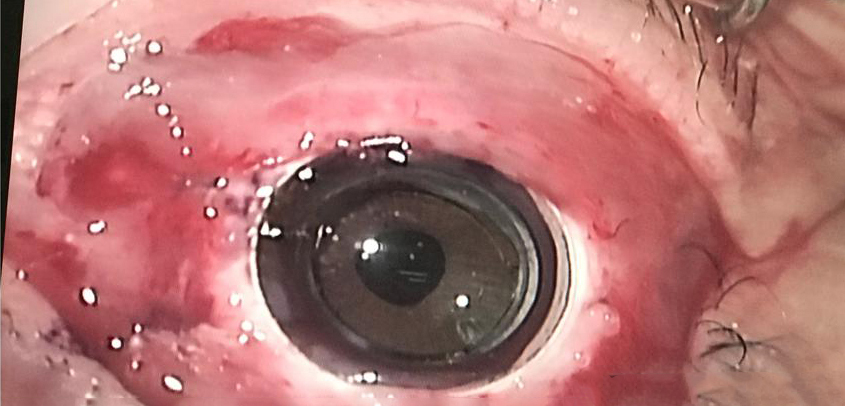

Source: Gilad Litvin, MD

The CorNeat KPro is described on the companyโs website as a โpatented synthetic cornea utilizing advanced cell technology to integrate artificial optics within resident ocular tissue. It is produced using nanoscale chemical engineering, which stimulates cellular growth.โ The CorNeat KPro is designed to integrate under the conjunctiva. Surgically, the CorNeat KPro implantation procedure is designed to reduce the time of โopen sky.โ

Irit Bahar, MD, MHA, who performed the first-in-human CorNeat KPro procedure in January 2021, said the surgical sophistication needed for most KPro procedures and the high rate of complications, due to the procedure or materials, motivated creation of the CorNeat KPro. Prof. Bahar said the first patient who received the CorNeat KPro has been having weekly follow-up with the results exceeding expectations thus far.

Gilad Litvin, MD, creator of the CorNeat KPro, noted that the synthetic nature of the device makes timing of the procedure more flexible, compared to those reliant on donor tissue.

โThe attachment site of the CorNeat KPro is external to the eye, thus no interference with ocular physiology occurs,โ Dr. Litvin explained. The device is also designed to allow for future anterior segment procedures.

โFollow-up is expected to be much simpler than previous [KPro] models. There is no need for protective contact lenses and no need for lifelong, local antibiotic treatment,โ Dr. Litvin said.